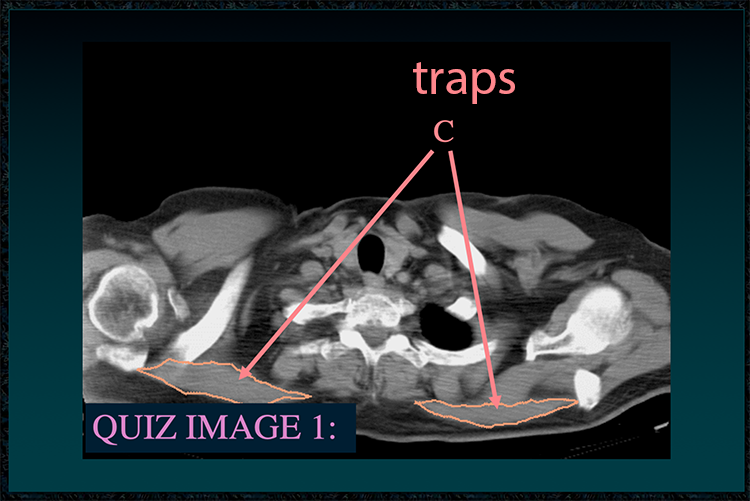

◂Chest Anatomy Review